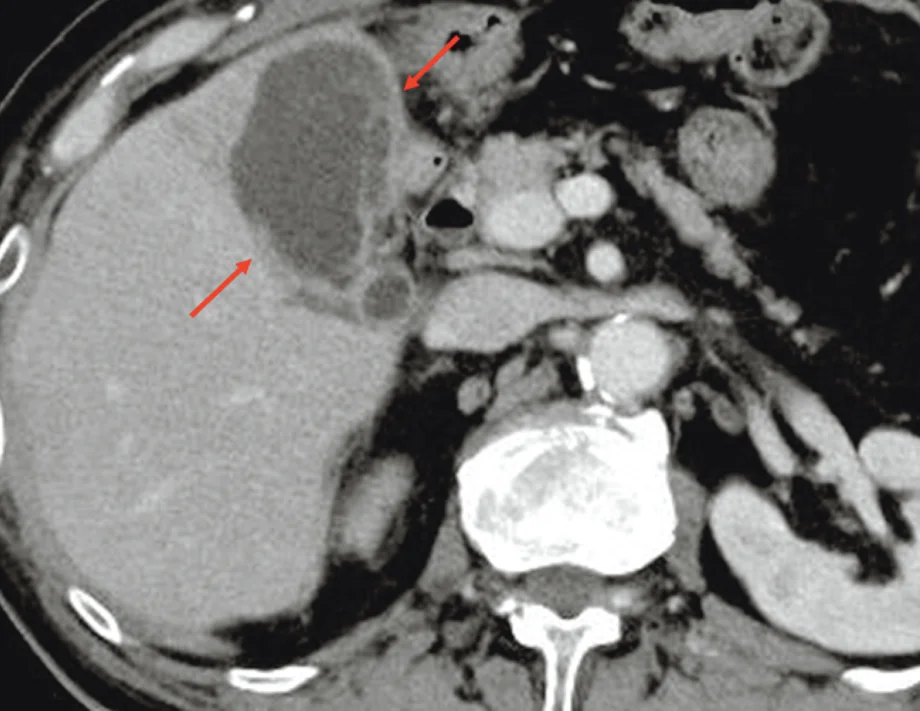

Cholangioscopy-guided guidewire insertion into the gallbladder using a novel thin cholangioscope under balloon enteroscopy in a patient with Roux-en-Y gastrectomy

Yuki Tanisaka, Shomei Ryozawa, Masafumi Mizuide. Akashi Fujita, Ryuichi Watanabe, Ryosuke Hamamura